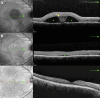

Results: Thirty-seven patients (40 eyes; mean age, 48.0 ± 11.9 years) had CSC and BALAD and were followed for a mean of 4.92 ± 6.65 months. The control group was comprised of 40 patients with CSC without BALAD (40 eyes; mean age, 48.2 ± 11.9 years). On clinical examination, BALAD was as a circular, yellowish macular lesion. On OCT, BALAD was a detachment of the ellipsoid zone with splitting of the photoreceptor inner segment. BALAD was associated with psychiatric disorders (p = 0.014), use of corticosteroids (p = 0.004), previous treatment for CSC (p = 0.041) and thickened choroid (p = 0.036).

Conclusions: BALAD in CSC differs from a typical CSC due to the presence of a circular, yellowish macular lesion, detachment of the ellipsoid zone, segmentation of the inner segment of the photoreceptor, a thicker choroid, the use of corticosteroids, and generally more aggressive previous treatments. These results suggest that BALAD may serve as a valuable biomarker for the severity of CSC and highlight the influence of inflammation and previous treatments.